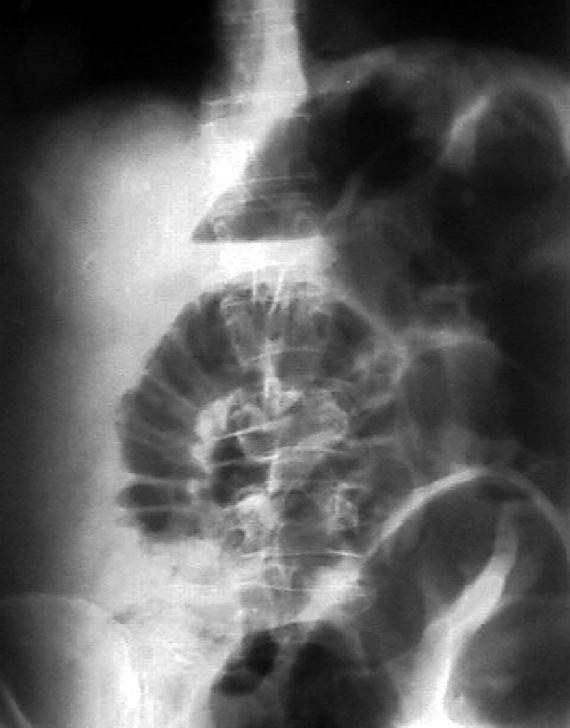

Больной К., 64 лет, поступил в стационар через 16 часов после возникновения схваткообразных болей внизу живота с жалобами на задержку стула и газов, тошноту, однократную рвоту. Страдает запорами в течение 8 лет.

Живот вздут, ассиметричен за счет выбухания его верхних отделов справа. При пальпации мягкий, не напряженный, болезненный по ходу толстой кишки. Левая подвздошная область «пустая». Симптомы Склярова и «Обуховской больницы» положительны. Определяется «шум плеска».

Произведена обзорная рентгенография органов брюшной полости (см. рисунок).

Каков предварительный диагноз?